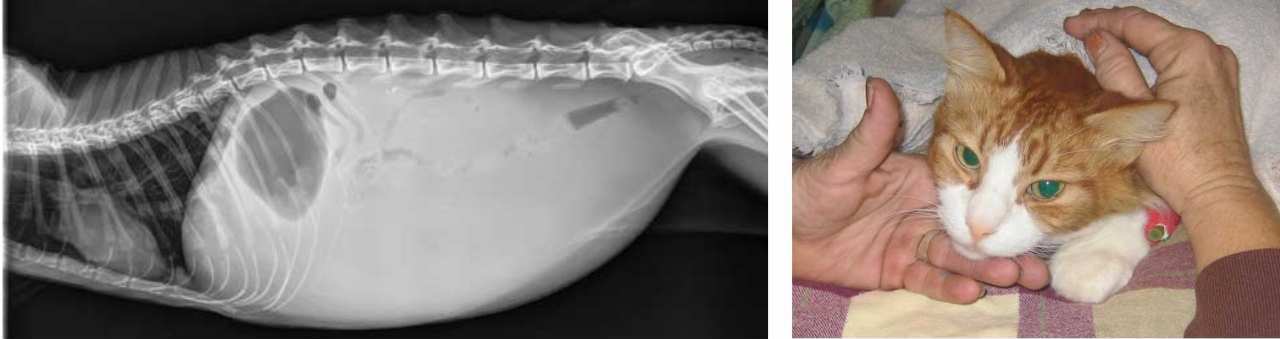

In FIP, that otherwise mild gut virus mutates. It leaves the intestinal tract and triggers a powerful immune response that begins attacking the cat’s own organs. This is why FIP can cause fever, lethargy, fluid buildup in the abdomen, and rapid decline.

Earlier this year, thousands of cats began dying on the Mediterranean island of Cyprus, often called the “island of cats.” The symptoms looked like FIP, but the number of cases raised serious concerns.